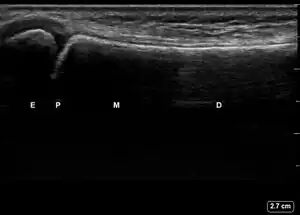

![]() Ultrasound lateral view of normal radius. E = epiphysis; P = physis; M = metaphysis; D = diaphysis. | |